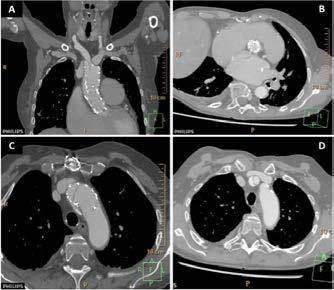

Se realizó una tomografía computarizada (TC) con contraste de forma emergente, que mostró una disección aórtica iatrogénica tipo A focal de origen en la zona 0 del cayado con extensión al tronco braquiocefálico derecho (1) sin afectar al resto de troncos supra-aórticos, cayado o aorta descendente (Figuras 1 y 2); además del hematoma

y disección de la arteria radial derecha, respectivamente. Finalmente pudo ser dada de alta tras 22 días de ingreso (Figura 3), bajo anticoagulación con acenocumarol.

Figuras 1 y 2: Prótesis aórtica migrada y disección aórtica focal tipo A, de origen en la curvatura menor del arco aórtico (zona 0) hasta la bifurcación de la arteria braquiocefálica derecha; sin afectación de del resto de troncos supra-aórticos, del resto del cayado aórtico o de la aorta descendente.